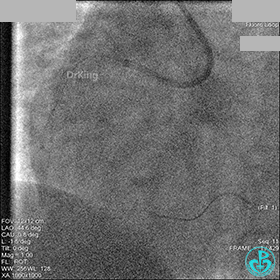

冠脉造影

入院次日冠脉造影显示粗大左主干末端中度狭窄,前降支开口严重狭窄,回旋支与前降支角度大,弥漫性长病变,严重狭窄,粗大右冠脉近中段弥漫性中重度狭窄。由于病变复杂,造影结束后先下台,择期再行介入治疗。